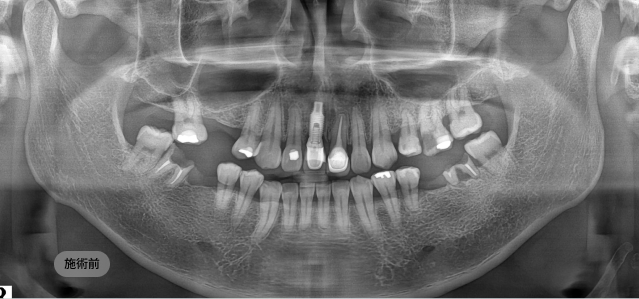

画面をドラッグして前/後を比較してみてください